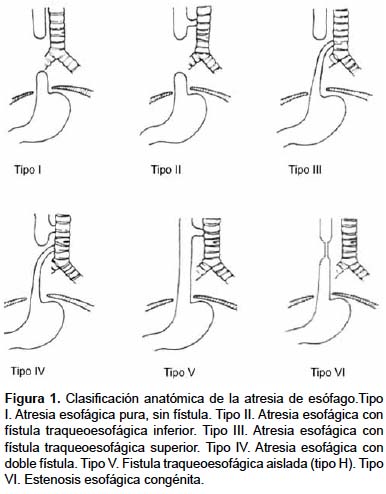

La AE se puede presentar con múltiples variantes. Existen diversas clasificaciones (algunos la clasifican con números y otros con letras) teniendo como base la anatomía que se identifique. Los datos más importantes para estas clasificaciones son el sitio de la fístula y la separación de los cabos. Se han reportado más de cien tipos de atresia de esófago, pero la clasificación original de Vogt (1929), modificada por Ladd en 1944 y Gross en 1953 se sigue utilizando hasta nuestros días.9 Los tipos anatomopatológicos descritos por Vogt son los más frecuentes. Si bien la tipo V ó fístula en H aislada y la tipo VI o estenosis esofágica no son en realidad AE, se incluyen de todas formas en algunas clasificaciones (Cuadro 1, Figura 1).